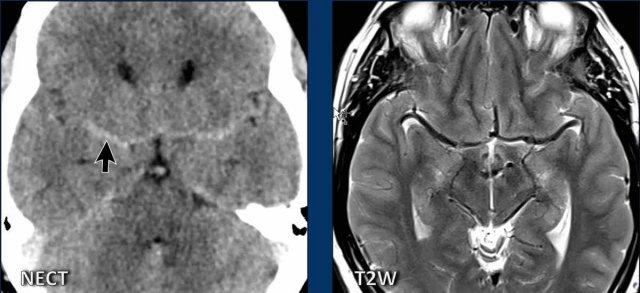

Hình ảnh

- Hạnh nhân tiểu não tụt thấp

Dấu hiệu không thật sự rõ ràng, một phần do có xảo ảnh chuyển động, nhưng hình dạng thân não không bình thường và có vẻ khoảng cách giữa cầu não và thể vú bị rút ngắn.

Có thể cũng có một số dấu hiệu ứ trệ tĩnh mạch. - Ngoài hạnh nhân tiểu não tụt thấp, hình ảnh trông bình thường.

- Bốn hình ảnh bên trái cho thấy các dấu hiệu điển hình của SIH với bờ lồi của xoang ngang, khoảng cách ngắn giữa thể vú và cầu não, và hình ảnh trung não bị võng xuống.

- Các hình ảnh bên phải không cho thấy các dấu hiệu này.

Bệnh nhân SIH đã được điều trị bốn lần bằng vá máu mù và đạt kết quả thành công.

Bệnh nhân Chiari type I đã được phẫu thuật giải ép vùng sọ-cổ và đạt kết quả tốt.